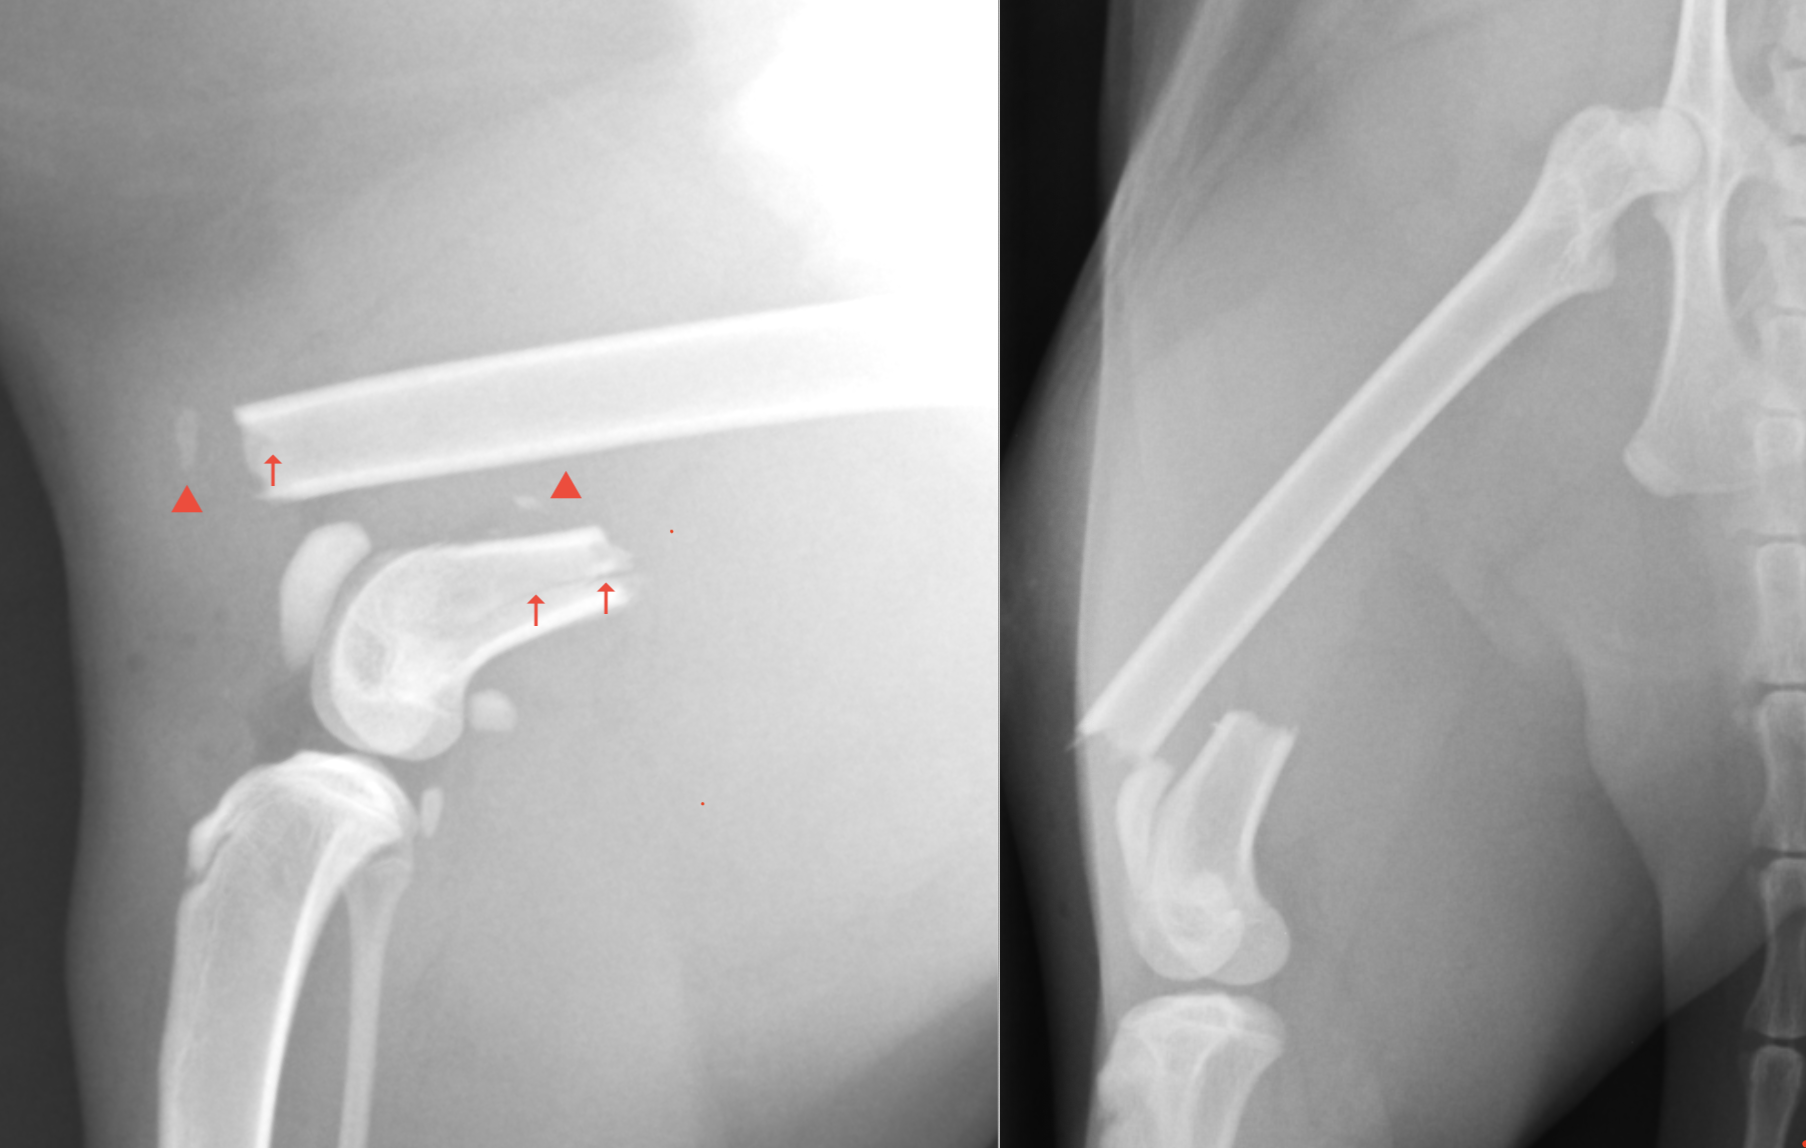

X線上では普通の横骨折に見えなくもないですが、よく見ると、小さい骨片や(矢頭)、ヒビ(矢印)が多数あるのが確認できます。

遠位がかなり短く、骨折線近くにはヒビが多数見えるため、ただの横骨折ではなく、粉砕骨折に近い病態であると考えられました。